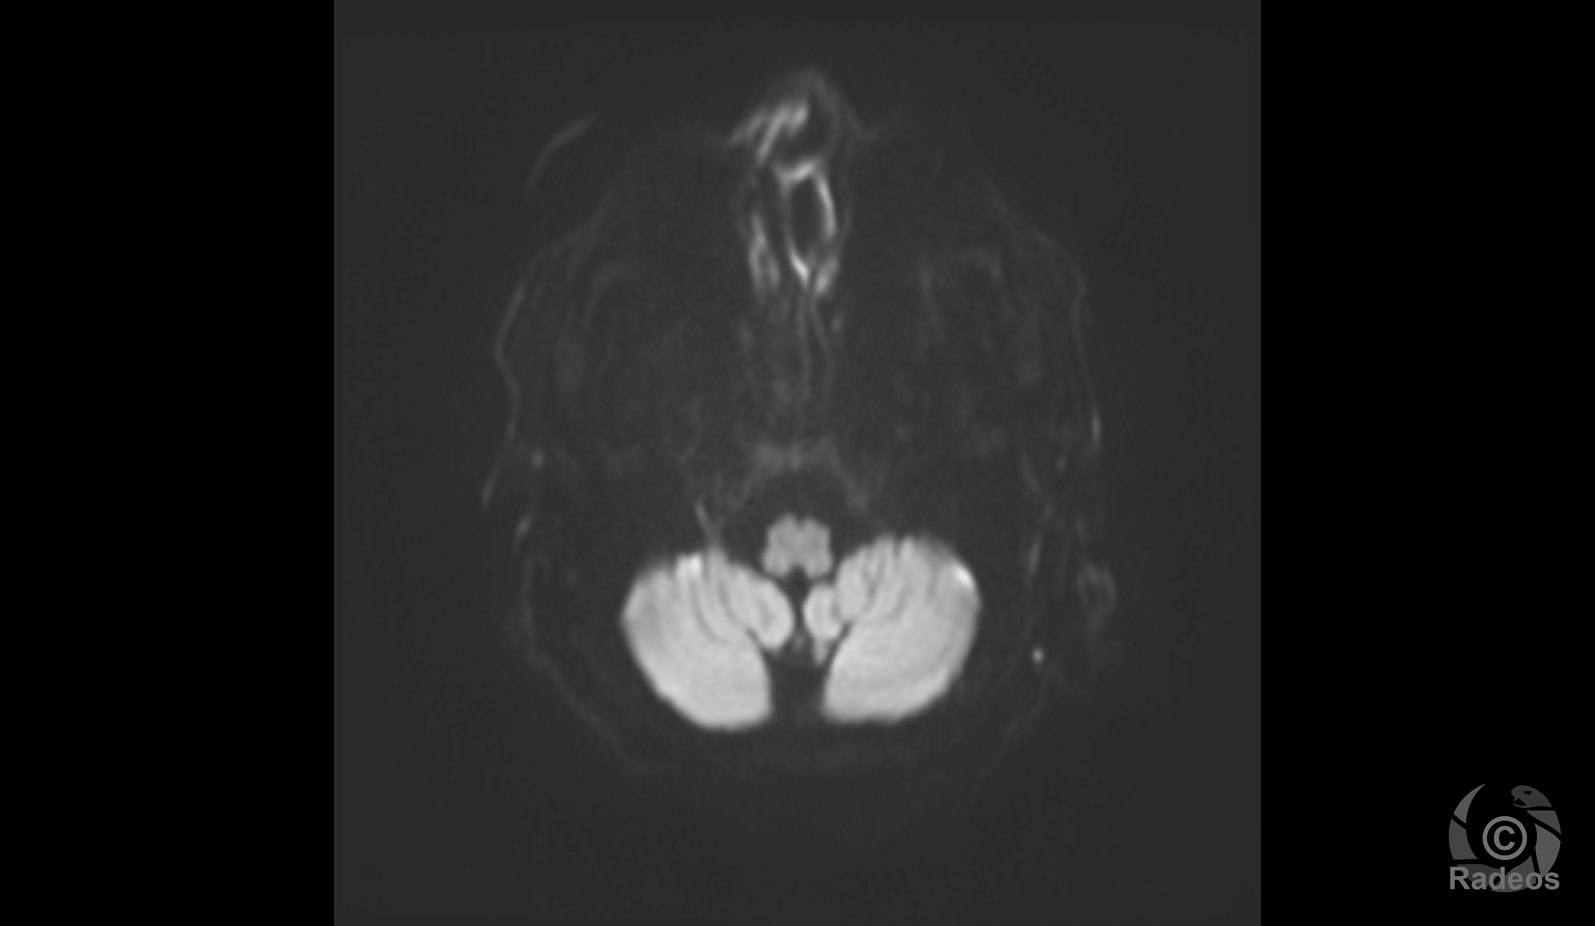

Aspect IRM d'une fibromatose profonde de la paroi abdominale. Découverte fortuite d'un angiome hépatique gauche.

Fibromatose profonde de type desmoïde